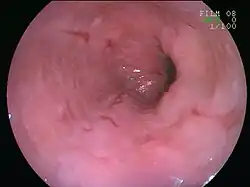

An esophageal ulcer visualized by esophagoscopy: the reddened area at 10 o'clock on the surface of the mucosa.

Esophagitis can be diagnosed by upper endoscopy, biopsy, upper GI series (or barium swallow), and laboratory tests.[4]

An upper endoscopy is a procedure to look at the esophagus by using an endoscope. While looking at the esophagus, the doctor is able to take a small biopsy. The biopsy can be used to confirm inflammation of the esophagus.